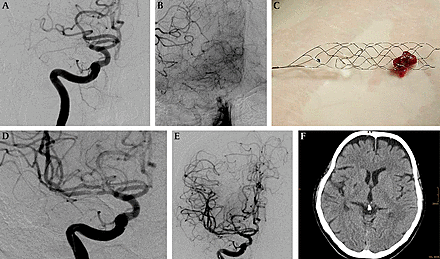

• Solitaire

Solitaire

Created intentionally as a neuroendovascular stent to treat wide neck aneurysms, the Solitaire flow restoration device has changed how acute ischemic strokes are treated. With lack of inventory during a stroke case in March 2008, doctors had no other choice but to use the off label stent if there was any chance in saving the patient's life. It worked.